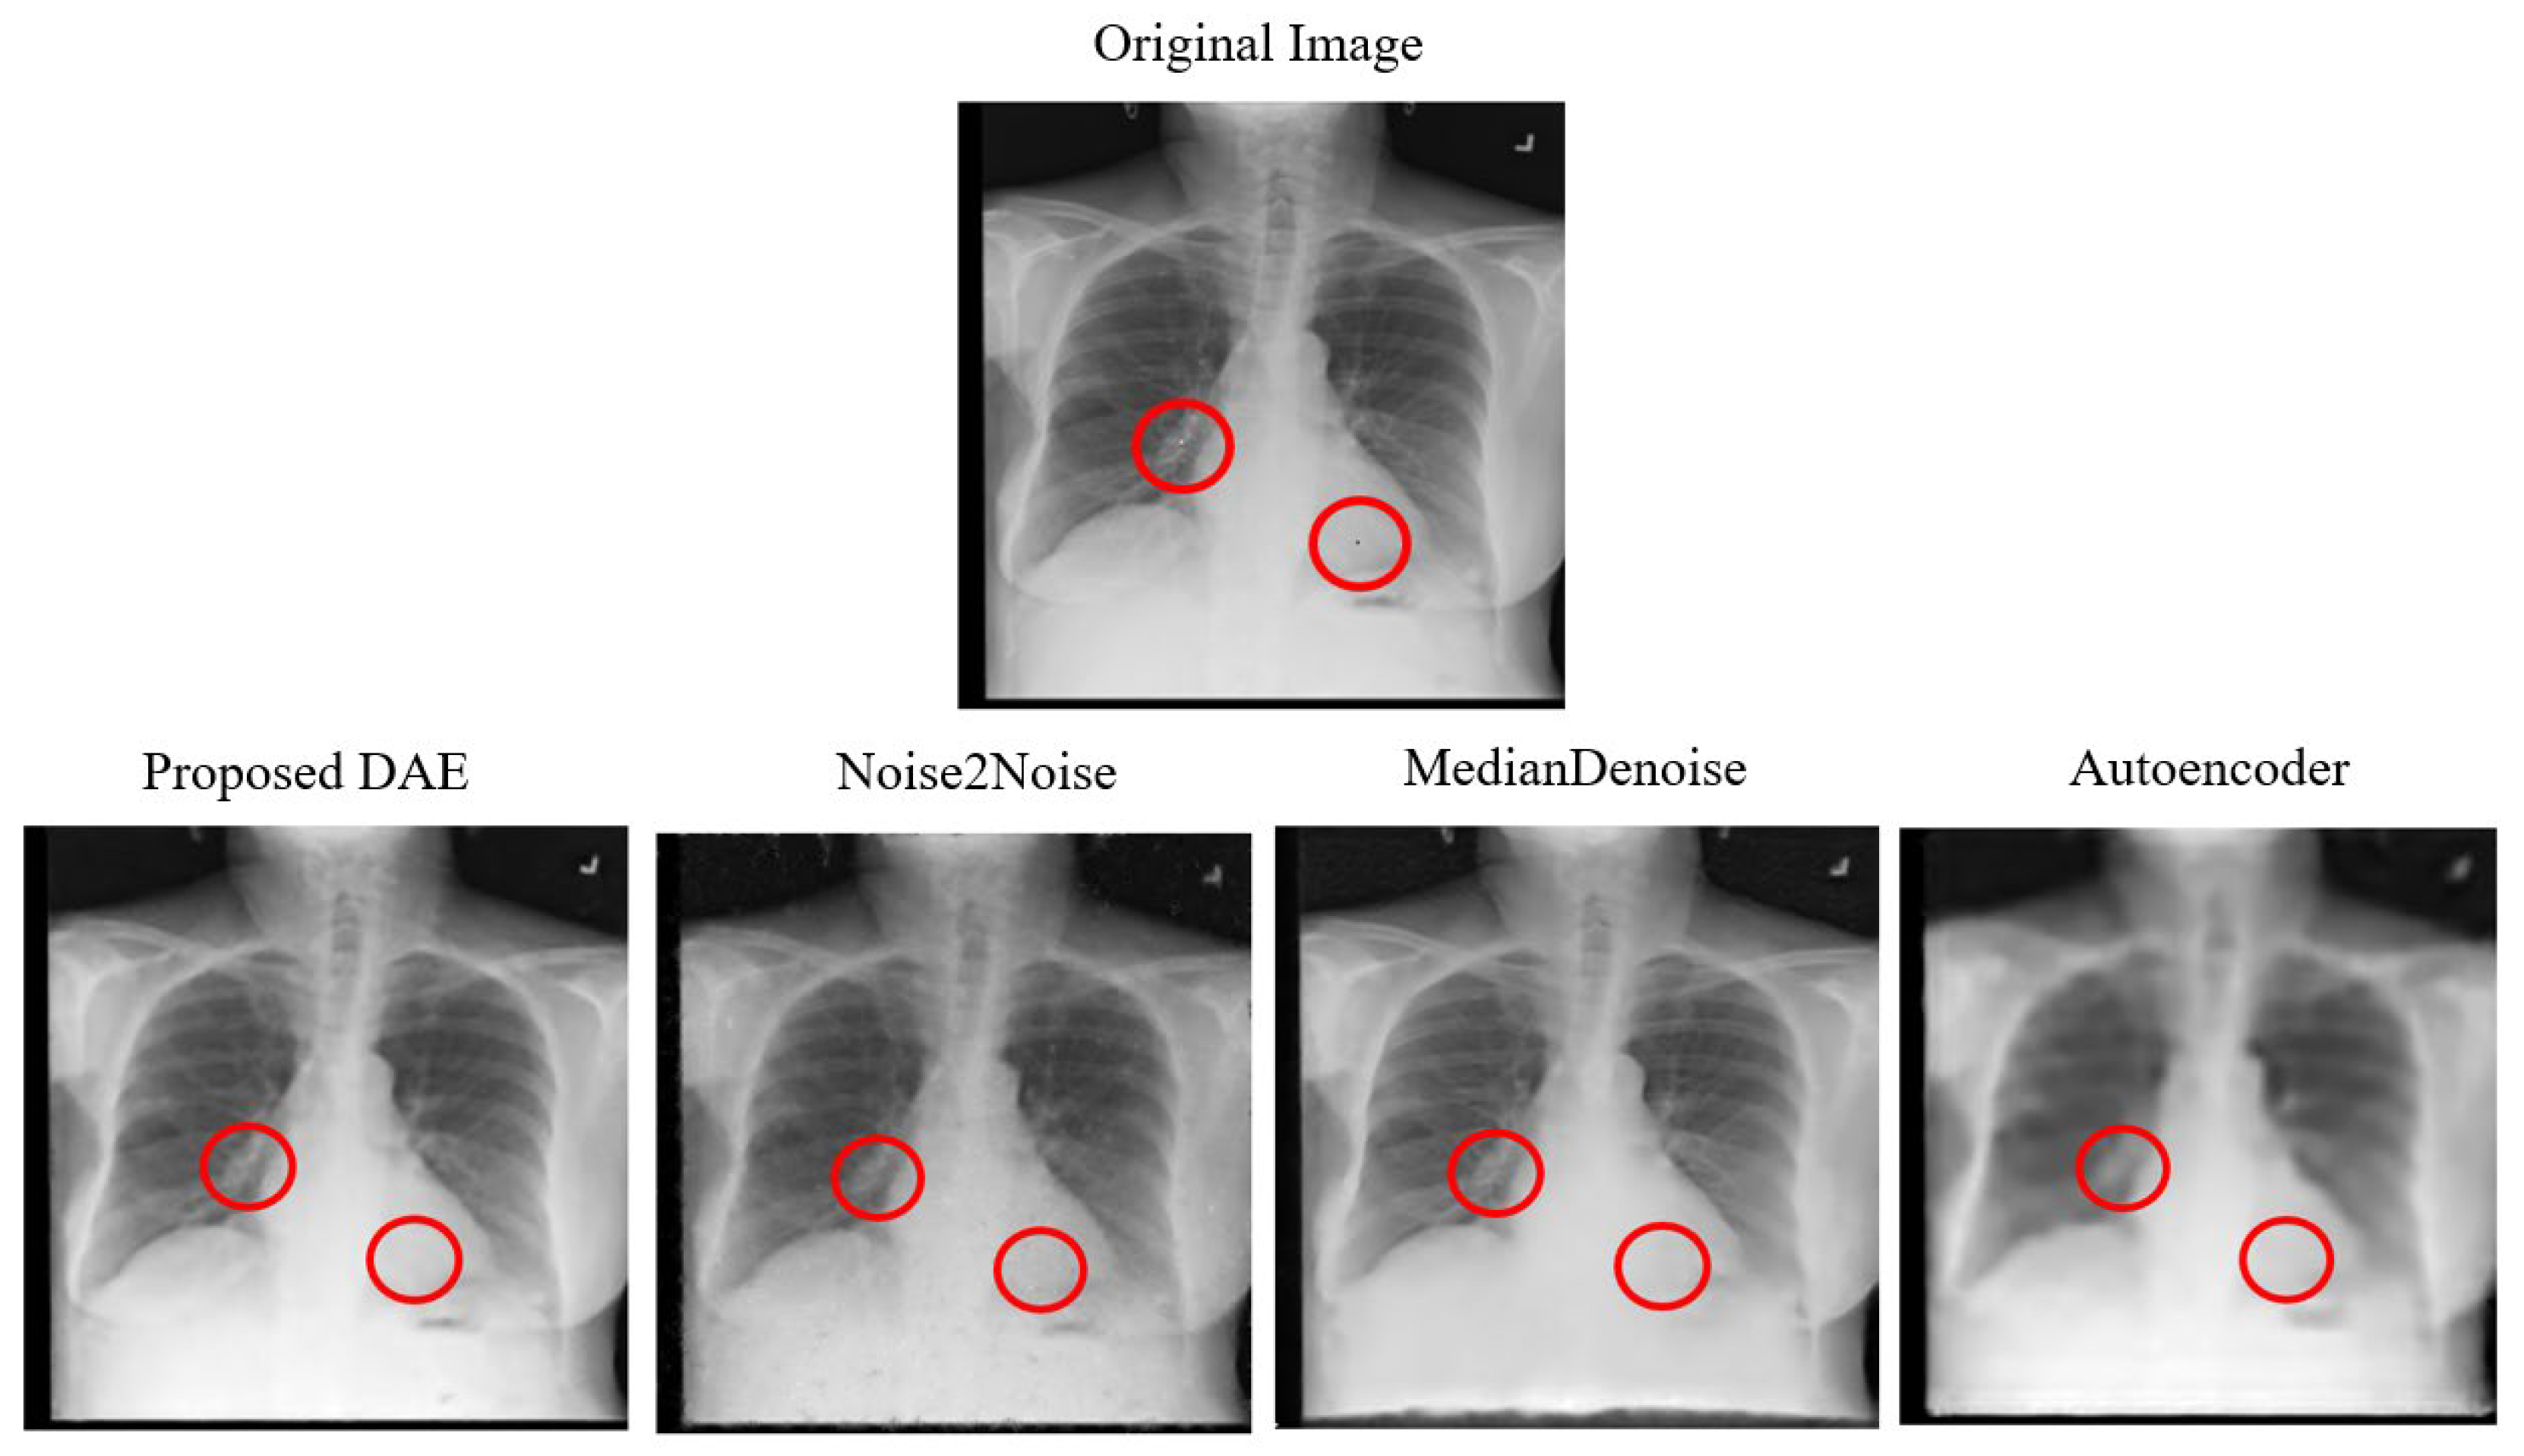

The average denoising results for each model on the Chest dataset are shown in Table 29 below. The images of the Chest that were successfully attacked with One-Pixel attacks are, respectively, shown in Figure 18, along with the reconstructed images after being denoised by each model.